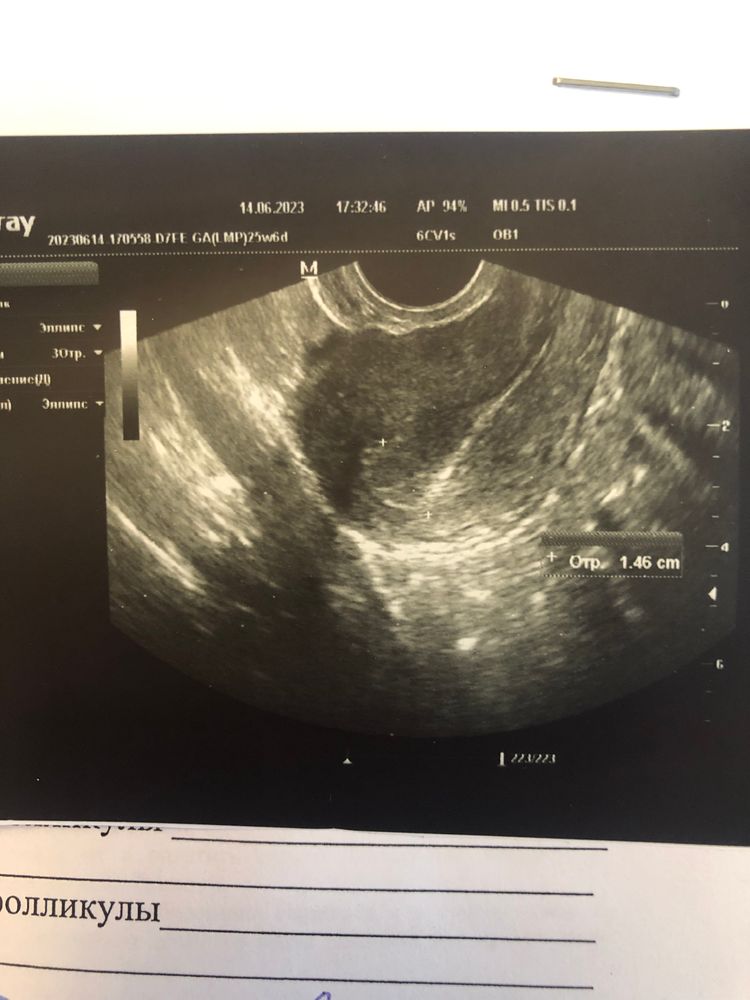

два дня назад сделала тест, цикл 30/33 дня, отталкивалась от 33, поэтому только в 1дз в обед. Эви показал хорошую // и она осталась, думала, ну все оно. Вечером не удержалась, ещё один эви, стало бледнее, но тоже точно есть. Подумала много воды выпила. Пошла на узи, из-за резкой боли, исключили внематочную, но и б не подтвердили(ну я этого и не ждала, главное, боли не из-за Патологий каких). Прошло 2 дня, повторяю тест, тоже эви, пока сухой чист. Высох и есть //, но она какая-то не понятная. Разве могут быть такие полоски при нормальной б?(

сверху на фото сухой тест сейчас, ниже 2 дня назад в обед и вечерний

Любовь, узи тоже странное дело, говорят ничего не видно, при этом фото чего-то прикрепили😅 хотя раньше ничего не давали

Надежда, понятое дело, что не увидят нечего. Рано ещё на УЗИ. Сдайте хгч